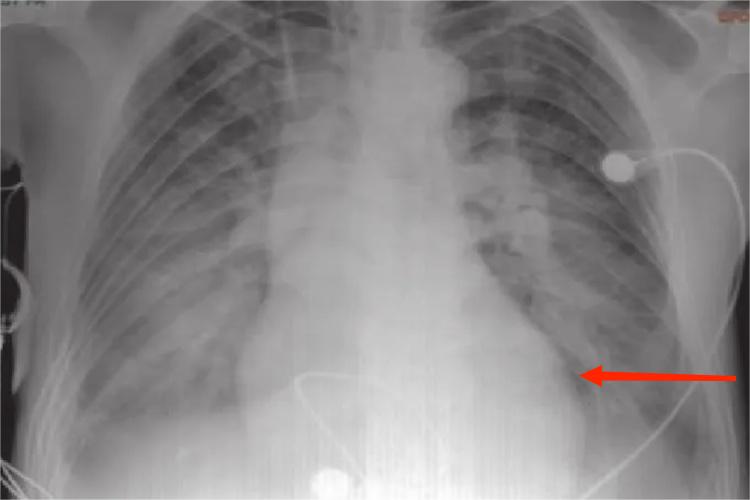

胸部X线检查:可见心影扩大,有心包积液时可呈烧瓶样改变。